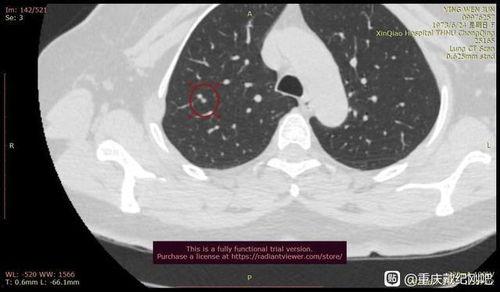

首先,得先弄明白什么是肺结节。肺结节,简单来说,就是肺部出现的小块阴影,通常直径小于3厘米。这玩意儿可能是由很多原因引起的,比如感染、炎症、肿瘤等。虽然很多肺结节是良性的,但也不排除恶性的可能,所以一旦发现,就得引起重视。